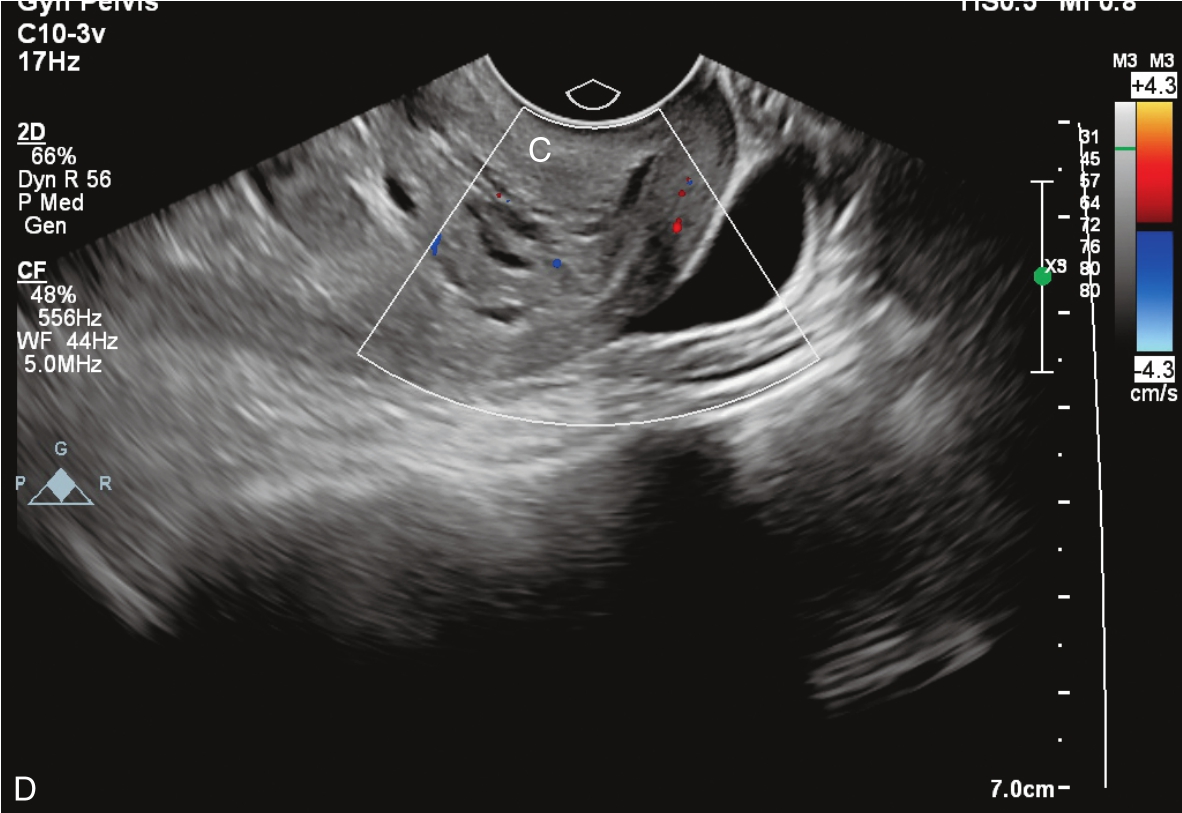

经静脉超声造影见图3-10-2及ER 3-10-1。注入造影剂后11s,宫腔内不均质稍强回声团块开始出现增强(图3-10-2A箭头所示),稍早于子宫肌层增强;注入造影剂后22s,团块根蒂似附着于宫腔上段宫底处(图3-10-2B箭头所示);注入造影剂后26s,宫腔内团块呈高增强,且其内造影剂分布不均匀(图3-10-2C箭头所示);注入造影剂后43s,宫腔内团块造影剂消退晚于子宫肌层(图3-10-2D箭头所示)。

图3-10-2 经静脉超声造影声像图

A.注入造影剂后11s;B.注入造影剂后22s;C.注入造影剂后26s;D.注入造影剂后43s。UT:子宫;MA:肿物。